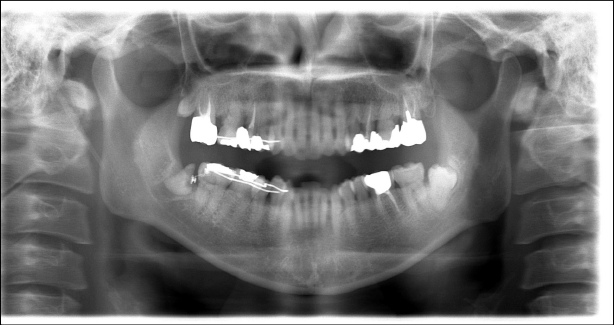

オルソパントモ所見

矯正治療終了時のレントゲン写真です。根っこの先端が神経と離れていることが確認できます。

この状態になれば安心であるため、抜歯いたしました。

この状態になれば安心であるため、抜歯いたしました。